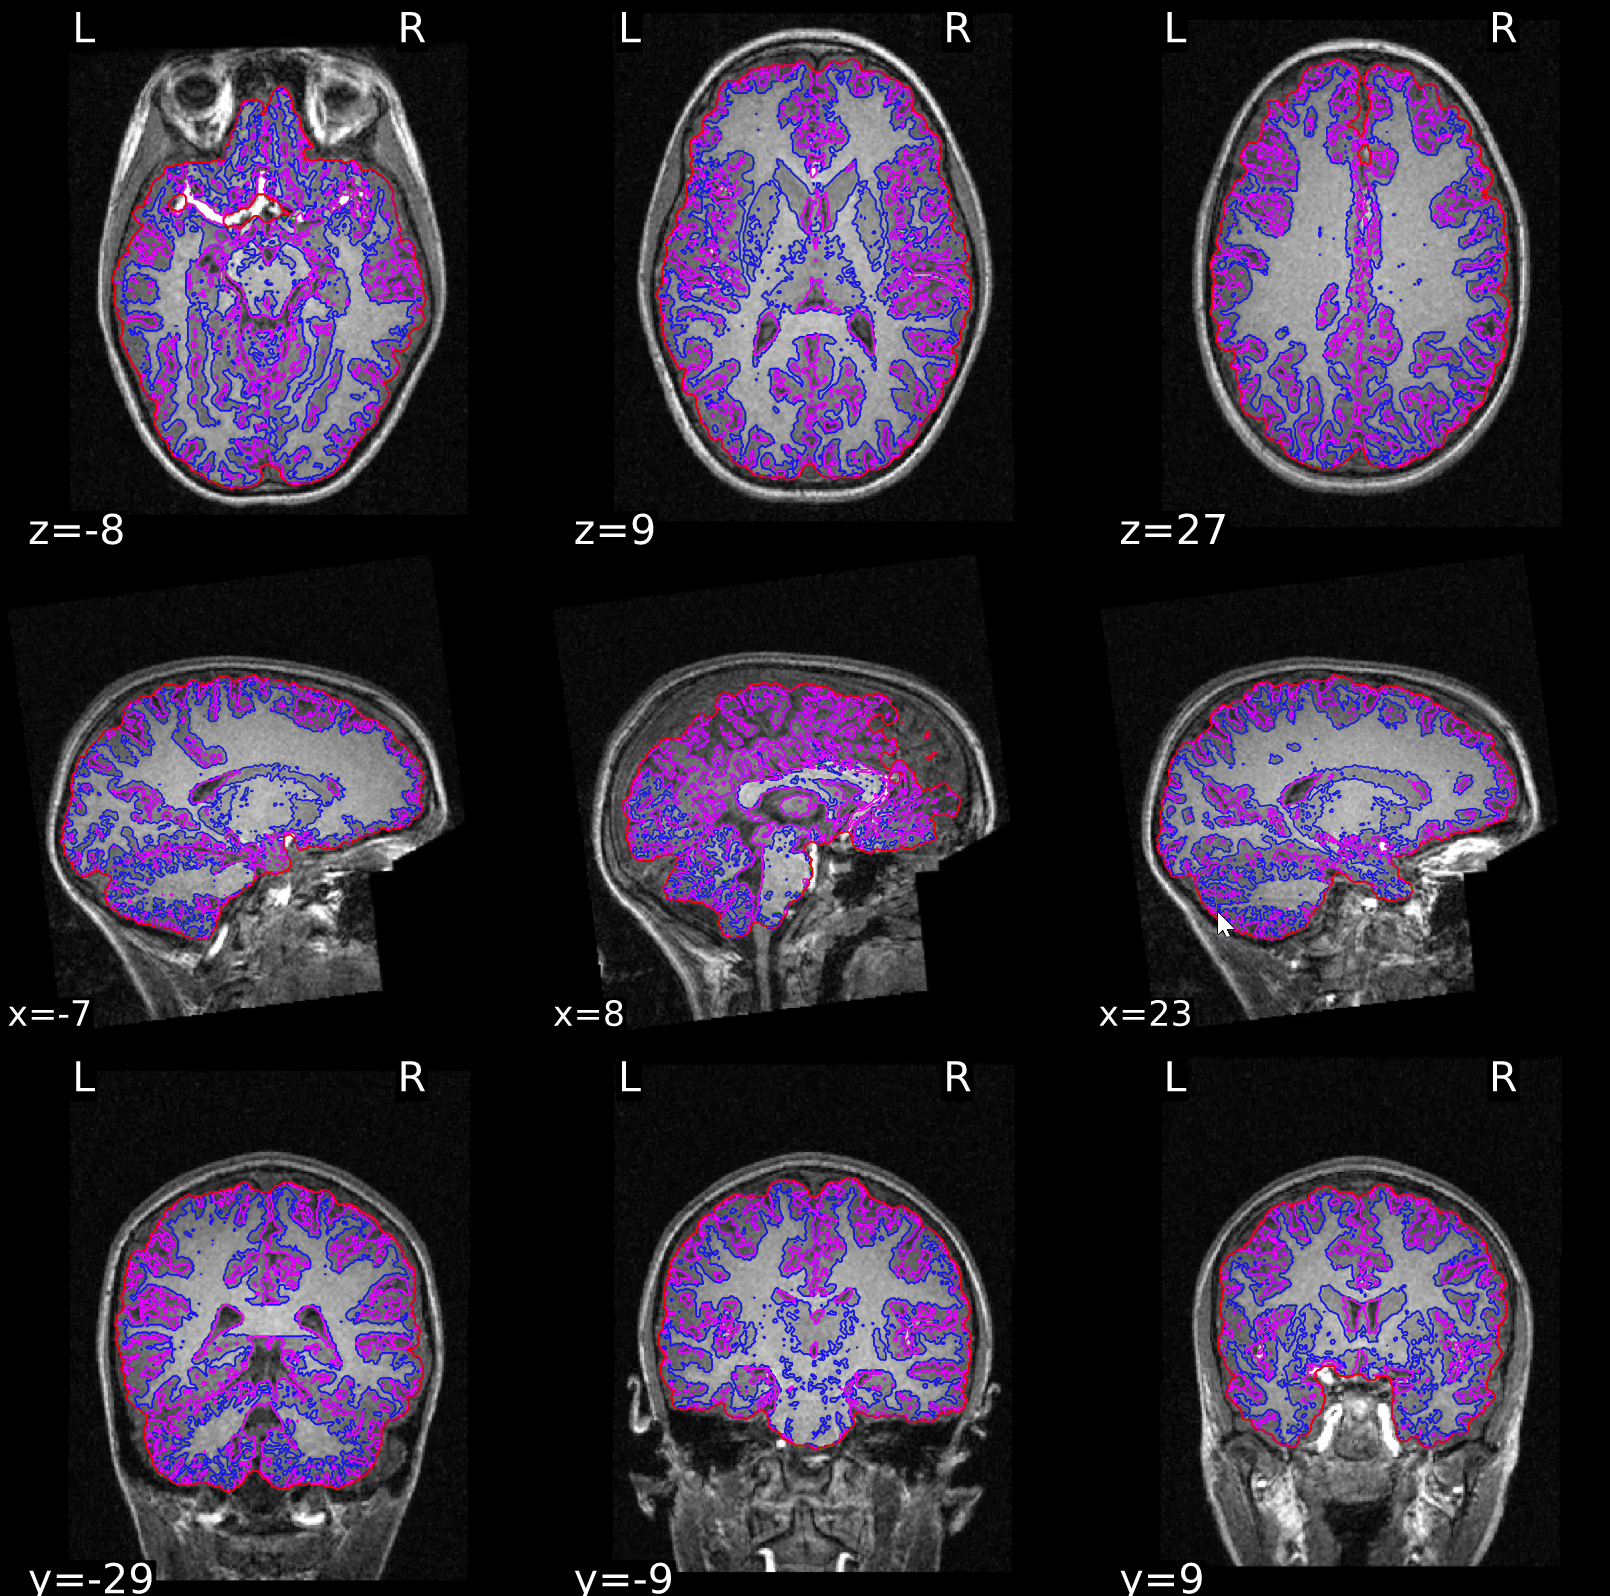

ds000108/reportlets/fmriprep/sub-24/anat/sub-24_T1w